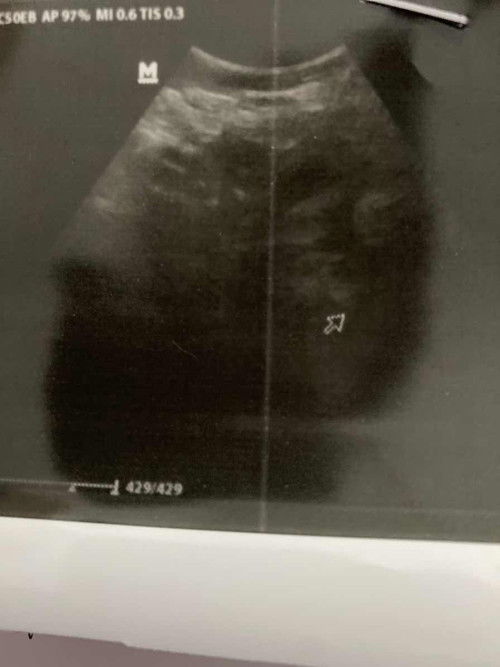

7 week masih penebalan rahim

hai moms, 7 week belum terlihat kantung dan masih penebalan rahim apakah normal atau tidak ya, kata dokter disuruh balik 4 minggu lagi , apakah ada yang pernah seperti ini ?